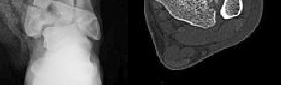

Figure 1 is the radiograph and Figure 2 is the CT image of a 45-year-old woman who fell about 20 feet off her balcony. These images show an isolated, open injury with a 3-cm open medial wound.

The best delayed definitive surgical fixation plan would include

Discussion: The timely administration of antibiotics has been shown to be the best initial treatment to reduce the incidence of infection following an open fracture. Life threatening injuries must first be addressed. But in this isolated open pilon fracture, antibiotics should be initiated early along with tetanus prophylaxis. Reduction and splinting would stabilize the fracture but these interventions should follow antibiotic coverage. Emergency department irrigation is controversial. Closed reduction and splinting, external fixation, CT scan, and delayed open reduction internal fixation would be the preferred sequence of management. External fixation to provide provisional limb stabilization would be indicated in this length unstable C type injury to provide soft tissue stabilization and prevent further chondral injury. Splinting alone would not prevent shortening and would not allow soft tissue recovery. CT scans prior to limb stabilization are not warranted because the patterns make more sense after the restoration of gross length, rotation and alignment in the external fixator. Initial fibular fixation is also not recommended in this case because the location of incisions could affect the definitive surgical tactic. In this multi-fragmentary fibular injury, anatomic reduction would be challenging and malreduction could occur and influence subsequent reconstructions. Delayed open reduction internal fixation is ideal after the resolution of soft tissue swelling.